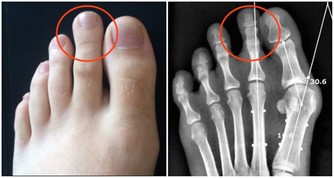

5、腎

正常人如果兩個腎,腎功能完全正常的情況下,摘除一個腎臟對人身體並沒有太大的損害,由於剩下一個腎完全可以再代償,一個人從生理上來說有一個腎臟,腎功能是正常的就可以達到日常需要。這是因為人體每個腎臟約有100萬個腎單位。

據研究,每個腎臟實際上只有1/10的腎單位進行工作,9/10的腎單位處於“輪流休息”狀態。

如果另一側腎完全正常的話,那麼對身體不會有什麼影響,不過不能做太多的運動。

ps:單腎沒關係,前提是腎功能沒問題!

如果一側腎功能很差,平日需特別小心保護剩餘的一個腎,

一旦剩餘的腎保護不好,出現了損害,就無法發揮過濾作用,

不能將有毒物質排出體外,久而久之代謝紊亂,最終形成尿毒症。